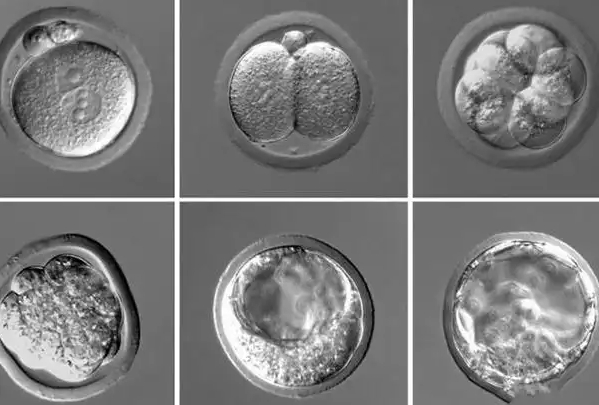

医生建议养囊的首要原因,是养囊过程能天然筛选出更具发育潜能的优质胚胎,从长远看提升胚胎移植成功率。卵裂期胚胎(第 3 天)的发育状态尚未稳定,部分胚胎看似形态正常,实则存在染色体异常或发育潜能不足,这类胚胎若直接移植,着床成功率较低,还可能增加早期流产风险。而囊胚培养是一个 “优胜劣汰” 的过程:只有染色体正常、细胞分化能力强的胚胎,才能在体外培养环境中继续发育,形成由内细胞团(未来发育为胎儿)和滋养层细胞(未来发育为胎盘)组成的囊胚。临床数据显示,囊胚移植的着床率通常比卵裂期胚胎高 20%-30%,且流产率更低,能减少因胚胎质量问题导致的移植失败,帮助患者更快实现妊娠,从整体治疗周期来看,反而可能降低 “反复移植” 的时间和经济成本。

患者担忧的 “养囊风险”—— 胚胎退化、可移植胚胎数量减少,本质并非 “培养过程导致的损失”,而是暴露了胚胎本身的发育缺陷。体外囊胚培养环境虽与体内存在差异,但正规生殖中心的胚胎实验室会严格控制温度、湿度、气体浓度(如二氧化碳、氧气),模拟体内输卵管和子宫的生长环境,确保培养条件稳定,避免因环境因素导致健康胚胎退化。若胚胎在养囊过程中停止发育,多数是因为胚胎自身存在染色体异常(如非整倍体)、基因缺陷或细胞分化能力不足,即使不养囊直接移植,这类胚胎也难以成功着床,甚至可能在着床后停止发育。因此,养囊过程中 “胚胎减少” 更像是一种 “精准筛选”,帮助医生排除无发育潜能的胚胎,避免将劣质胚胎移植到子宫内,减少无效移植,让患者避免因 “移植劣质胚胎” 浪费时间和精力。